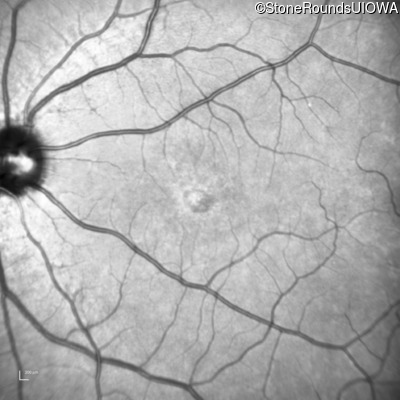

Age at visit: 17 years

OD OS

This 17 year old female first noted problems with her visual acuity around age 13 when she had trouble seeing the projector from the back of the classroom.